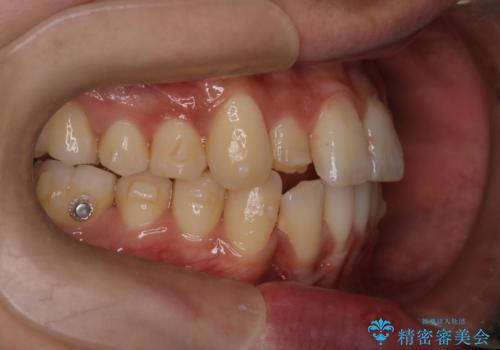

- 凸凹を治したいと来院された患者様です。

インビザラインにて、遠心移動を行いながら綺麗に配列することができました。

側切歯が低位の場合、反対咬合を改善した後に挺出させるのはワイヤーの方が適しています。